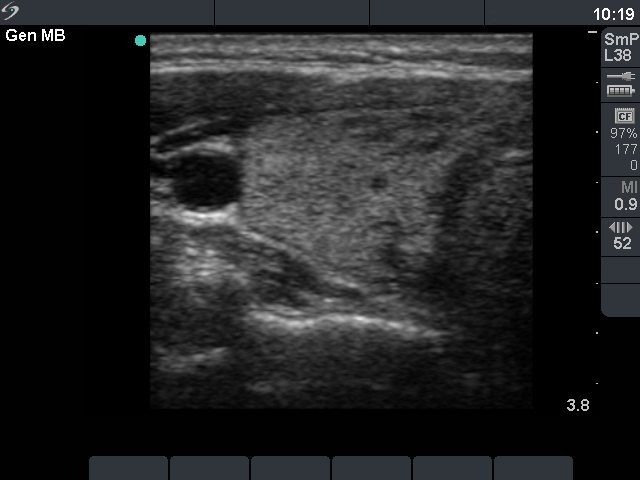

Follow-up examination 13 months later (second row of sonographic images and the cytological pictures)

Clinical presentation : the patient was well. We wanted to discontinue the medical therapy.

Palpation : no abnormality.

Functional state: euthyroidism on daily 5 mg methimazole and 50 microgram levo-tiroxin (TSH 2.99 mIU/L, FT4 13.7 pM/L).

Ultrasonography: compared with the former examination both the size, the echogenicity and the vascularization had normalized except for small hypoechogenic areas with less than 10% of echogenicity index. However, a hypoechogenic nodule with microcalcifications and irregular borders appeared in the left lobe.Cytological picture: there isn't any colloid on the smear. Thyrocytes in irregular clusters with nuclear crowding and overlapping. Thyrocytes are enlarged. Many follicular cells exhibit groove and inclusion. Cytological diagnosis: papillary cancer.

Histopathology: papillary cancer.

Comment: in our practice this was the third patient with a coexistent Graves' disease and papillary cancer in whom we could not detect the focus of papillary cancer on the first examination. The basic echo structure in the active phase of the autoimmune process was identical with the focus of papillary cancer, therefore the nodule was hidden. The only chance to detect the carcinoma is to repeat ultrasonography until the basic echo structure will be normalized.